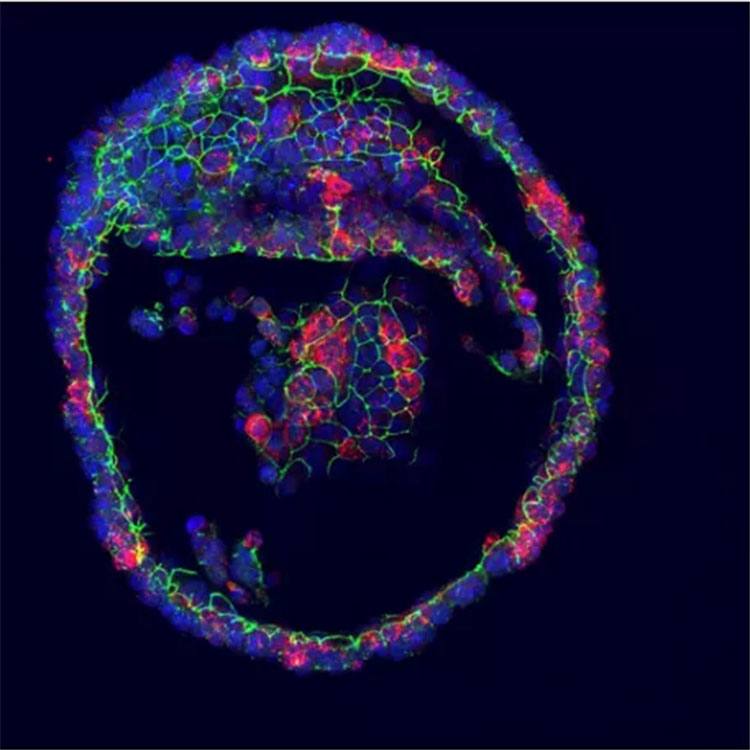

就像人們因為疼痛而哭泣一樣,這些器官也會因為去甲腎上腺素等化學刺激而哭泣。類器官的細胞在類器官的內部流出眼淚,這被稱為腔。于是,類器官就會像氣球一樣膨脹。因此,類器官的大小可以作為淚液產生和分泌的指標。進一步的實驗表明,淚腺中的不同細胞構成眼淚的不同成分。這些細胞對催淚刺激的反應也不同。

人類類器官產生眼淚,紅色為眼淚產物LCN2